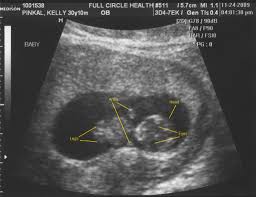

You may be wondering when those pesky early pregnancy symptoms will start to fade or getting ready to share your big news with the world. This device is kind of like a microphone placed on the belly. Pregnancy symptoms & belly pictures. But if you are feeling some uncomfortable symptoms, things may seem like they're dragging. Ultrasounds are usually done in the first trimester to confirm a viable pregnancy, confirm the heartbeat, and confirm molar or ectopic pregnancies and also to assess abnormal gestation. A month later hemmorage healed on it own and was back to normal activity. 10 weeks 3 days pregnant. Ultrasound image of identical twins at 10 weeks, these babies share the same sac. By conducting a scan, she will be able to identify whether or not your baby is developing normally. Avoid wearing tight and constricting clothes. Pregnancy week 10 learn what is happening with your baby's development in week 10. His toes and fingers have taken a distinct form and started developing fingernails as well. At 10 weeks of pregnancy, the foetus weighs about 4gm and measures around 3.1cm from crown to rump.

At this stage, the baby is growing even more rapidly! Your baby at 10 week pregnant has started developing tissue and you can see his arms and legs forming. Expansion of the uterus, muscles and ligaments to accommodate a growing baby are all part of the growing bump. Ultrasound image of fraternal twins at 10 weeks, you can see the thick membrane separating the babies. Fetus measured at 10 weeks 4 days and all looks good for now :) violation reported. Bloating can still be a contributor to a perceived bump and not everyone will see a baby bump at 10 weeks. At 10 weeks pregnant, you're getting close to the end of your first trimester. Check baby fetal development signs, baby movement, nutrition, diet suggestions. At 10 weeks of pregnancy, the foetus weighs about 4gm and measures around 3.1cm from crown to rump. Pregnancy week 10 learn what is happening with your baby's development in week 10. Learn about being 10 weeks pregnant. Blood tests aren't generally necessary during early pregnancy except as a tool to determine what sort of care you might need. Those cells are tested for genetic abnormalities.